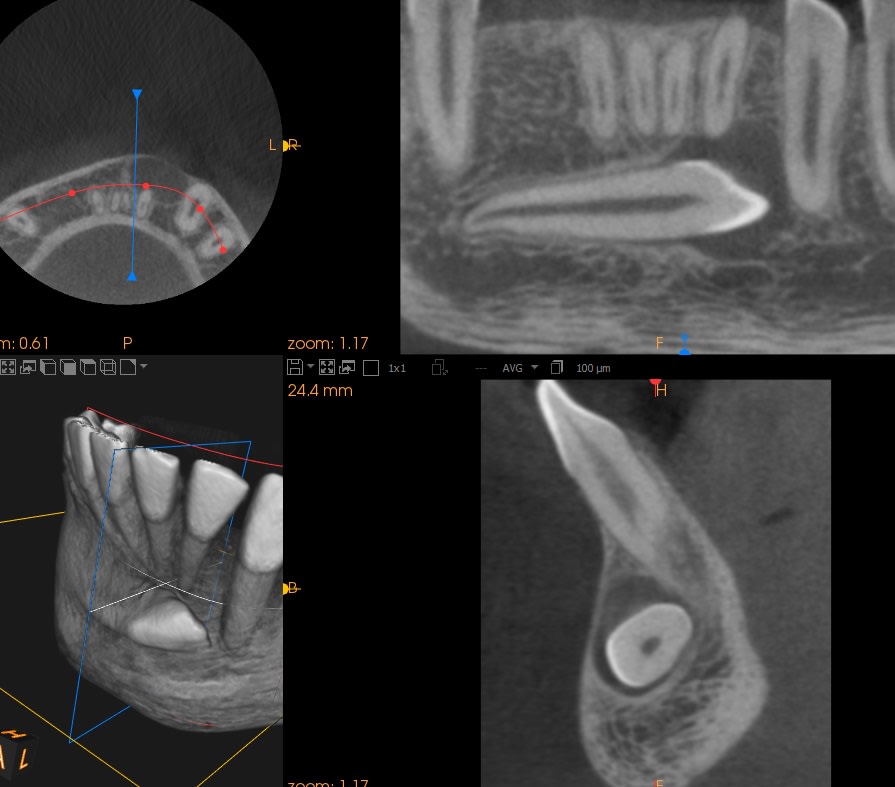

L'apex de la 43 est en bonne position, ce qui veut dire que tu n'a qu'a faire un mouvement de tipping pour redresser la dent.

Un miniviss au niveau de la canine de lait vas avoir une composante trop lingual, et comment vas tu controlé la direction de traction ? Elle sera imposé par la position de la visse.

Une simple boucle en TMA au niveau de la molaire te permet de contrôler completment la direction de la traction.

L'activation de la force est aussi constante ce qui est un autre plus.

Un simple TPA de 6 a 6 suffit largement comme unité d'ancrage dans ce cas

Pour ton cas comme pour le mien il faut une composante occlusal et légèrement vestibulaire et pas occlusal lingual.

Voici un exemple de traction de canine incluse inférieure. Il faut absolument laisser les incisives inférieures totalement libres pour qu'elles puissent un peu se déplacer spontanément si nécessaire.

La supériorité du CT8 sur n'importe quel autre ancrage pour tracter les canines incluses tient en particulier à sa longueur qui permet des forces légères (25g), avec une grande amplitude de mouvement en direction contrôlée. Prévois bien un retour du fil suffisamment long après sa pliure au niveau de la ligature pour avoir de la marge. Tu pourras alors le déplier et le replier différemment en cours de traitement si tu veux, un moment donné, modifier la direction de la force. On a en effet toujours tendance à le couper trop court.